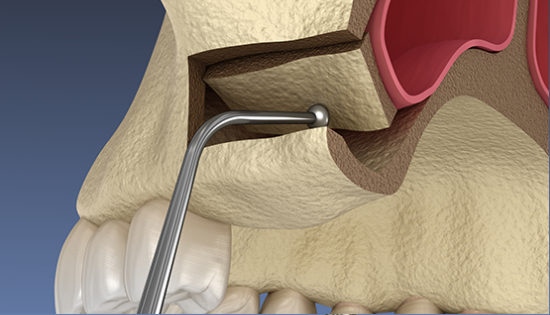

임플란트 수술시, 상악동과 잇몸뼈 사이에 뼈가 남아 있지 않았을 때 상악동막을 들어올리고 빈 공간에 뼈를 이식하여 임플란트 식립을 위한 공간을 확보하는 수술을 상악동 거상술이라 합니다.

밀도가 높고 두꺼운 턱뼈가 구성된 아래턱과는 달리 위턱은 얇은 뼈 위에 코와 광대 사이 빈 공간에 식립해야 하는 고난도 수술로 임플란트 수술 경험이 많은 의료진에게 받는 것이 중요합니다.